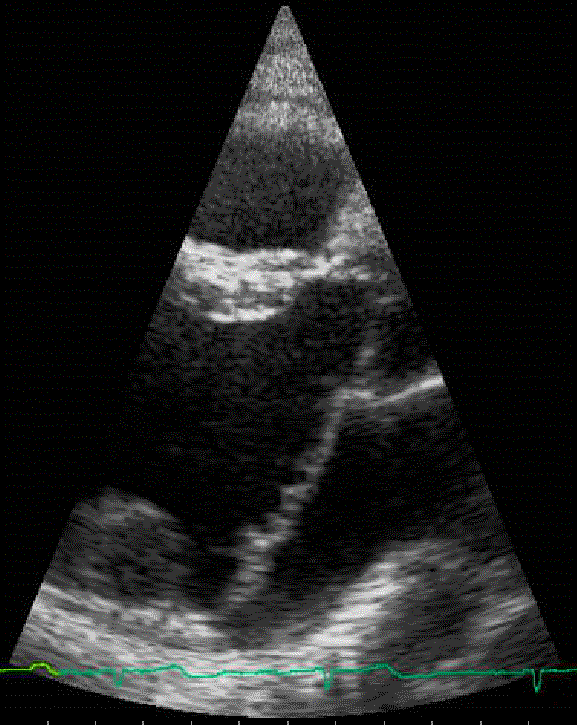

Here

is an animation clip of the acutal echocardiogram, showing

the prolapsing valve. The animation is paused at the prolapse

so that it can be clearly seen.

Click here for a larger, slow motion version The

image below captures the frame where the prolapse can most

clearly be seen. There is a line superimposed

over the approximate point where (according to the Cardiologists)

the valve should be stopping during a normal closure if

it

wasn't

prolapsing.

In other

words, the two leaflets shouldn't go to the right of the

line: